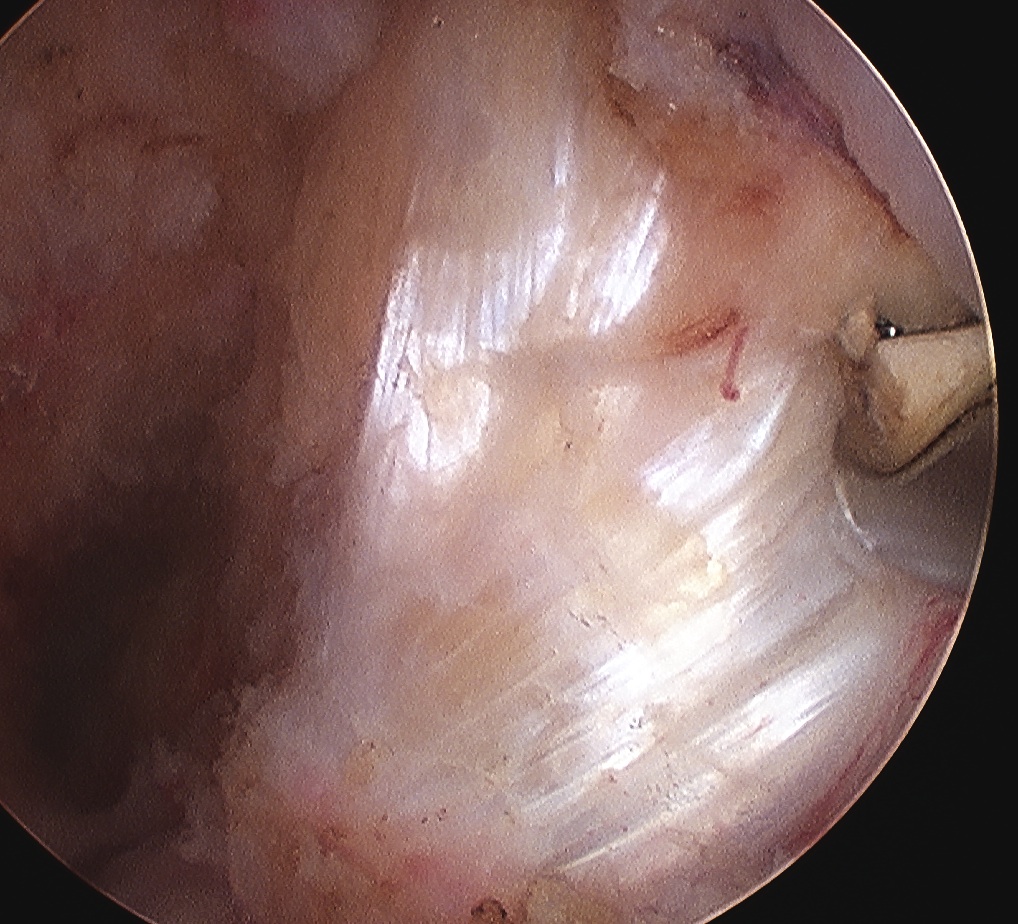

Arthroscopy

May miss tear as is extra-synovial

Chronic PCL tear from femur

Acute PCL femoral avulsion

Apparent ACL laxity due to PCL tear and posterior tibial sag; ACL tension restored with anterior drawer